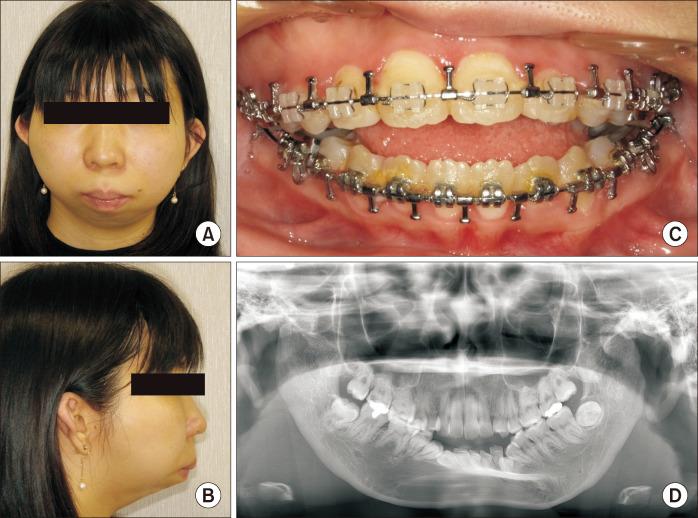

Untreated mandibular condyle fractures in childhood can result in significant jaw deformities, such as mandibular retrognathism, open bite, and facial asymmetry, which may necessitate surgical intervention in later years. Surgical approaches vary depending on the severity of the condition, including mandibular surgery alone, maxillomandibular surgery, or mandibular distraction osteogenesis (MDO). This report highlights a case involving mandibular retrognathism and open bite with condylar dislocation and malunion caused by untreated pediatric condyle fractures. Key challenges in this case included excessive anterior mandibular movement, irregular morphology of the mandibular ramus caused by malunion from fracture healing, and anteromedial dislocation of both condyles, all of which posed significant surgical complexities. The surgical approach combined Le Fort I osteotomy with MDO to perform maxillary impaction and mandibular advancement, followed by a secondary genioplasty. Notably, the dislocated temporomandibular joints were left untreated. Two years postoperatively, no relapse or recurrence of open bite was observed, and the dislocated condyles showed no positional and morphological changes, reflecting favorable outcomes. To our knowledge, this is the first reported case of orthognathic surgery combined with MDO for bilateral dislocated mandibular condyles, making it a valuable contribution to clinical practice.

儿童期未经治疗的下颌髁突骨折可导致严重的颌骨畸形,如下颌后缩、开颌和面部不对称,这可能在日后需要手术干预。手术方法因病情严重程度而异,包括单纯下颌手术、上颌下颌联合手术或下颌骨牵张成骨术(MDO)。本报告重点介绍了一例因儿童期髁突骨折未经治疗导致下颌后缩、开颌伴髁突脱位和骨不连的病例。该病例的主要挑战包括下颌前部过度移动、骨折愈合导致的骨不连引起的下颌升支形态不规则以及双侧髁突向前内侧脱位,所有这些都带来了重大的手术复杂性。手术方法结合了Le Fort I截骨术和MDO,以进行上颌骨上移和下颌骨前徙,随后进行二期颏成形术。值得注意的是,脱位的颞下颌关节未进行治疗。术后两年,未观察到开颌复发或再发,脱位的髁突也未出现位置和形态变化,显示出良好的效果。据我们所知,这是首例报道的正颌手术联合MDO治疗双侧脱位下颌髁突的病例,对临床实践具有重要价值。